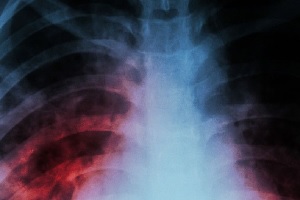

A tuberculose continua sendo uma das principais doenças mortais do mundo: só em 2014, infectou 9,6 milhões de pessoas e matou cerca de um milhão e meio de pacientes. A única vacina disponível, Bacillus Calmette-Guérin (BCG), funciona bem para prevenir a doença grave em crianças, mas ainda não produz resultados decisivos contra a doença do pulmão, especialmente em países onde a tuberculose é mais comum.

Fonte: Universidade de Oxford. Imagem: Divulgação.